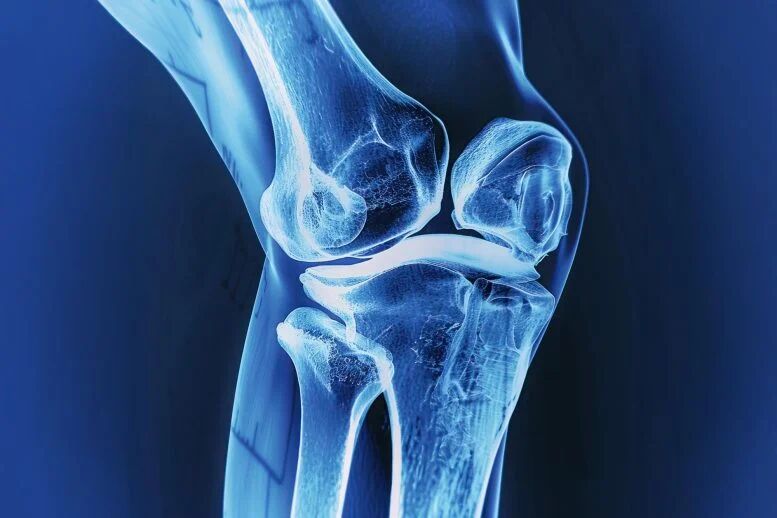

در این مطالعه، گروه پژوهشی روی عوارض رایج مرتبط با ایمپلنتهای استخوان تمرکز کرد. میلیونها نفر در سراسر جهان با ایمپلنتهای فلزی لگن یا زانو زندگی میکنند. بسیاری از این ایمپلنتها بهمرور زمان نیاز به تعمیر پیدا میکنند، زیرا یا بهخوبی با استخوان پیوند نمیخورند یا استحکام خود را از دست میدهند.